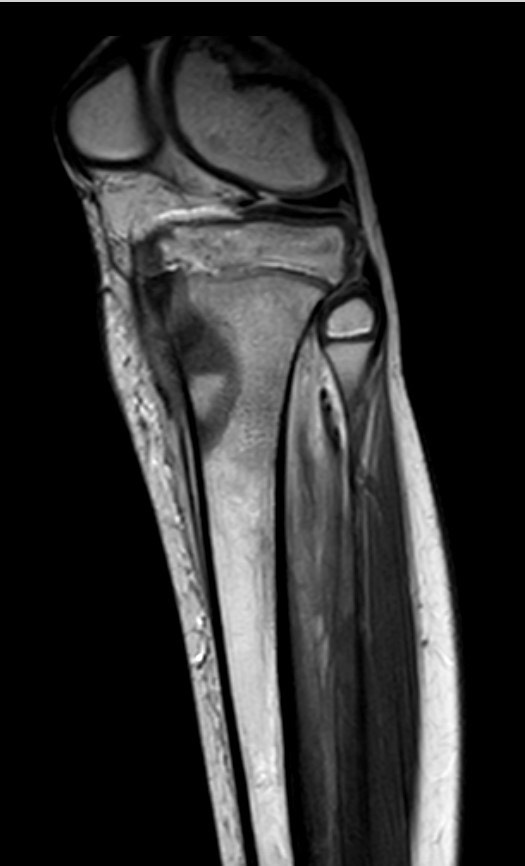

1331. Мальчику 14 лет с жалобами на периодические боли в верхней трети правой голени и нарушением походки в виде хромоты на правую ногу, выполнена магнитно-резонансная томография, заболеванием, которое может соответствовать клинико-рентгенологической картине, считают _____ проксимального отдела _____ кости